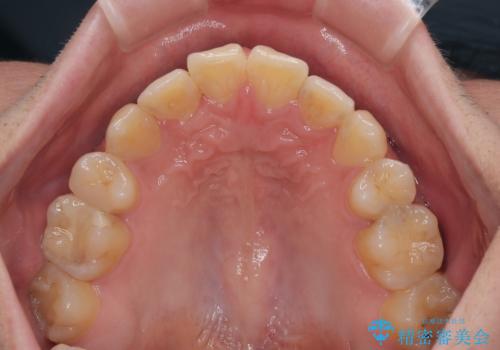

- 高校生の時に行った抜歯矯正の後戻りを気にして来院された患者様です。

インビザラインでの治療を希望されていて、デコボコの程度が中等度であり、安価なパッケージにて対応可能と判断されたため、インビザライン・モデレートを用いて矯正治療を行うこととしました。

インビザライン・モデレートは、製作できるアライナーの枚数に制限があるため、移動可能な量に限りがあるものの、インビザライン・ライトよりも枚数が多いため、幅広い症例に対応可能です。